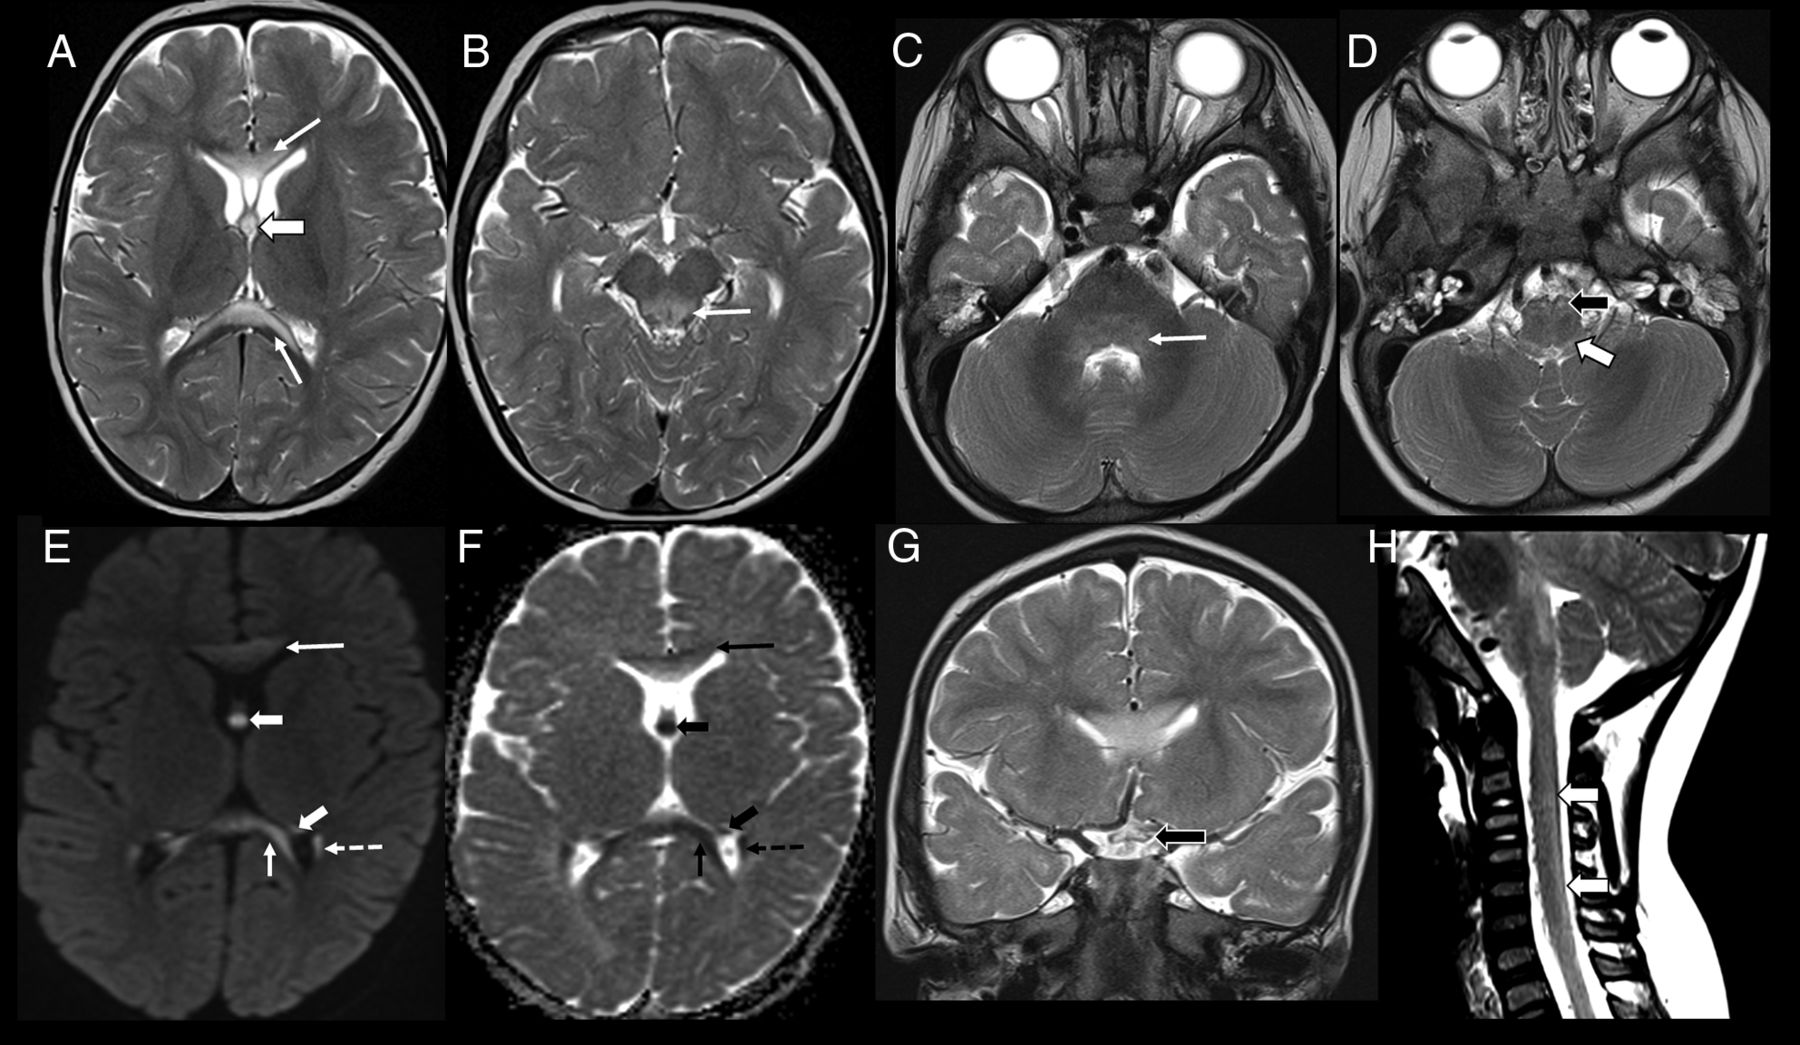

Imaging appearance in the early childhood age group (patient 8, 18 months of age). Axial T2-weighted images show hyperintense lesions involving the genu and splenium of corpus callosum (A, arrows), forniceal columns (A, arrowhead); dorsal midbrain including the periaqueductal gray matter (B, arrow); dorsal pons (C, arrow), medullary pyramids (D, black arrowhead), and dorsal medulla (D, white arrowhead). Axial DWI (E) and ADC (F) images show restricted diffusion involving the corpus callosum (arrows), fornices (arrowheads), and tapetum (dashed arrow). Coronal T2-weighted image (G) shows involvement of the optic chiasm (black arrowhead). Sagittal T2-weighted image of the cervical spine (H) shows faint hyperintensity involving the dorsal cervical cord (white arrowheads).